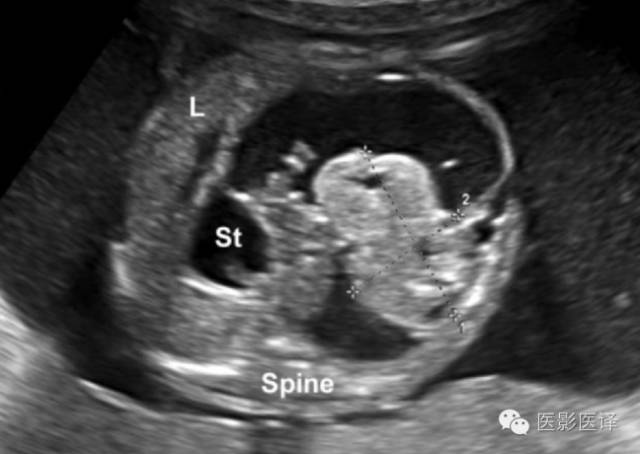

图20.寄生胎。23周胎儿超声横断面显示一个长约36mm的半囊半实性包块(标尺标示)。肿物邻近脊柱,将胃(St)推挤至中线右侧,肝脏(L)向上移位。包块的位置及胃移位的方式表明其来源于腹膜后。卵巢囊肿不太可能在这个阶段的孕期出现。